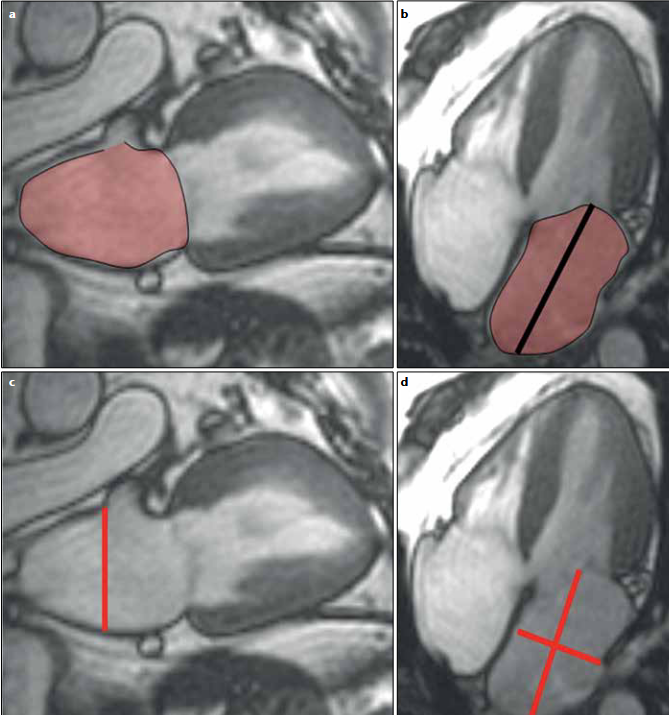

The LA volumes are derived using the biplane area-length method, which is based on the formula (Nacif et al., 2012).